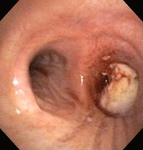

Стеноз дыхательных путей на фоне гранулематоза с полиангиитом (ранее именуемого гранулематозом Вегенера)

Из коллекций Хосе Фернандо Сантакруза, дипломированного врача, члена Американской коллегии специалистов в области торакальной медицины, DAABIP, и Эрика Фолка, дипломированного врача, магистра наук; используется с разрешения